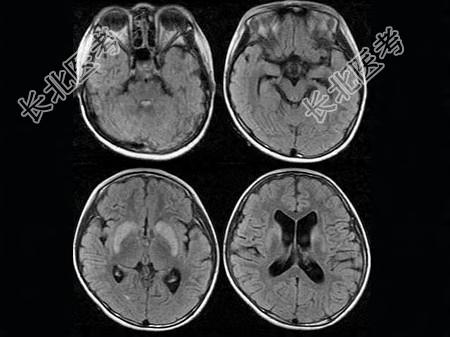

- 单项选择题女,12岁, 进行性肢体震颤1年余,多次出现发音困难, CT、MRI检查如图所示,最可能的诊断为  (    )

A、肝豆状核变性

B、脑萎缩

C、双侧基底节区多发梗死

D、脱髓鞘改变

E、脑积水